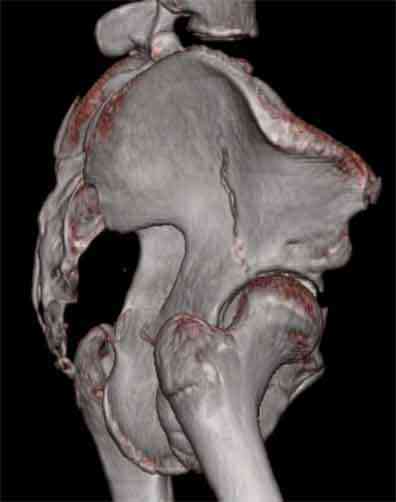

Не смог разглядеть на представленных картинках частичное повреждение левого КП, повреждение Денис1-2 справа? 3Д реконструкции в инлет и боковой проекциях убедительно не демонстрируют типа повреждения задних отделов тазового кольца(справа боковая масса скомпремирована), Наверное, у тебя есть возможность оценить тип перелома крестца по прямой проекции 3Д.

По вертлуге- смог разглядеть только изолированный перелом передней колонны.

Насколько я понял из твоего письма, обращенного к анонимному vit, ты не видишь показаний к реконструкции перелома. Я бы взялся за реконструкцию(илео-ингвинальный доступ), хоть прошел и месяц после травмы: боковая 3Д показывает смещение нагрузочной зоны впадины, что однозначно будет способствовать разрушению хряща головки и впадины( особенно у 16 летнего пациента с ожидаемым высоким уровнем активности) + изменение геометрии впадины за счет неустраненного смещения фрагментов колонны (КТ, 3Д данные).

На мой взгляд, без реконструкции этот сустав обречен (концепция вторичной конгруэтности в данных условиях работать не будет), реконструкция дает шанс на восстановление функции сустава.

Сравнивая боковые проекции 3Д реконструкций, разница переломов очевидна: в предыдущем случае на боковой проекции не видно было ступени нагрузочной зоны суставной поверхности - это и объясняет приличную функцию сустава.